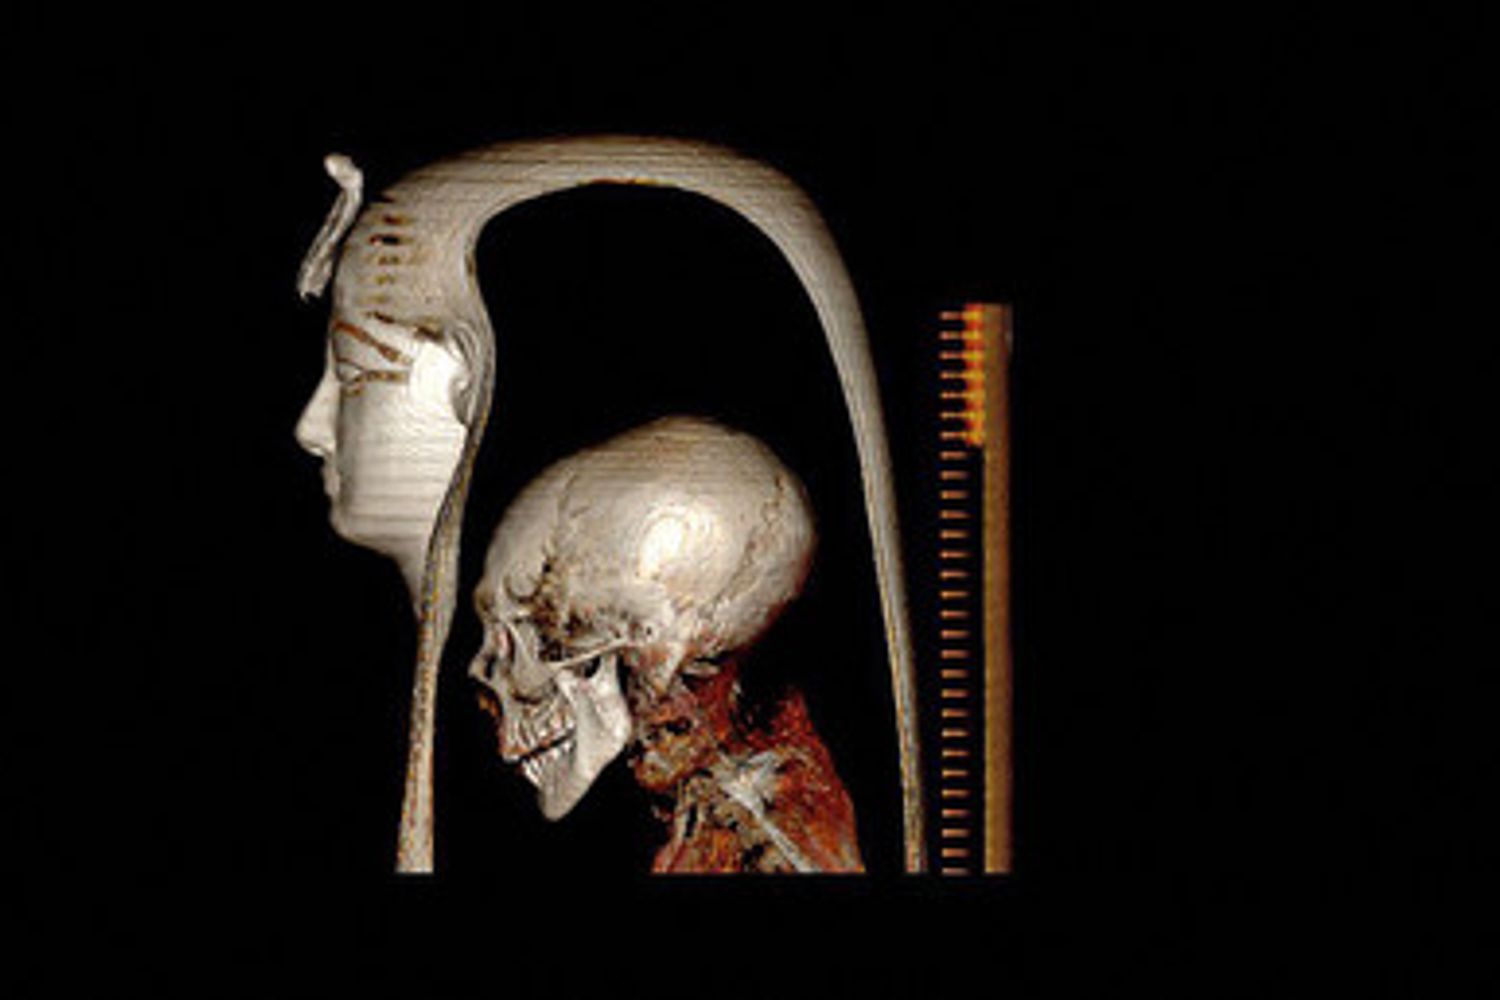

- Ricostruzione digitale della testa di Amenhotep I

Dettagli che mai erano stati ricostruiti prima, svelati dai ricercatori dell’Università del Cairo grazie a una tac, la tomografia assiale computerizzata: con lo scanner, un'autopsia digitale ha rivelato il volto e l'età in cui morì l’uomo che regnò nel potentissimo Egitto tra il 1525 e il 1504 a.C, come racconta Frontiers in Medicine.

“Ci siamo trovati dinanzi a un uomo di circa 35 anni, alto 1 metro e 69 centimetri, circonciso, che indossava circa 30 tra amuleti e manufatti, alcuni dei quali pezzi unici. Dalla ricostruzione emerge una grande somiglianza con il padre: entrambi avevano i capelli ricci, un naso molto sottile e una dentatura sporgente”, sintetizza Sahar Salem, direttore del progetto Mummie dell’Università della capitale egiziana.